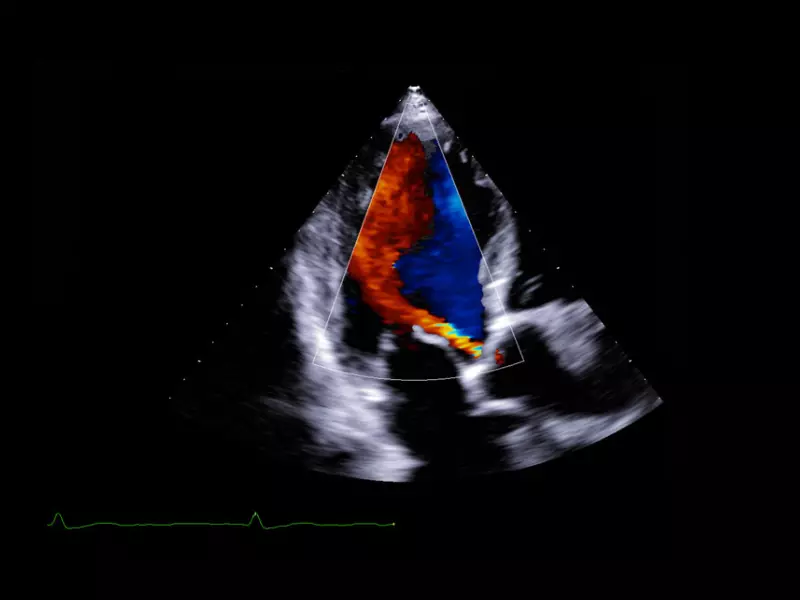

MyLab™X90 - Cardiovascular 07

MyLab™X90 - Cardiovascular 07